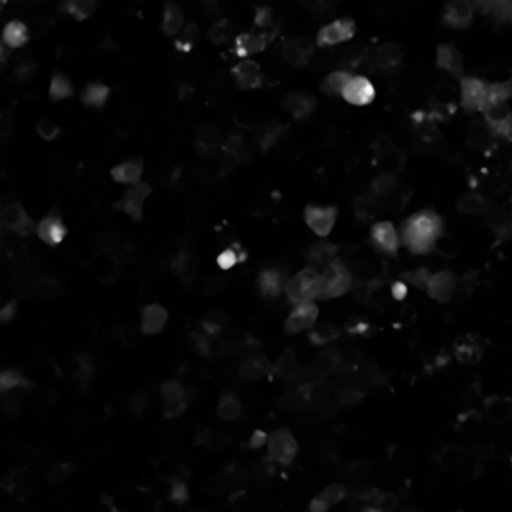

Data employed in this study consist of a live-cell imaging dataset comprising video recordings acquired from CLSM experiments on HL-1 CM networks, which have been widely characterised in previous studies [10, 7, 12, 18]. To visualise intracellular signals, HL-1 networks were loaded with Fluo-3 AM, a fluorescent reporter used extensively in biological imaging of signalling dynamics. Changes in Fluo-3 AM FI, associated with CM contraction, were recorded for at pixel resolution in AVI video format [7, 12]. Each recording produced a multi-temporal frame stack of frames for subsequent processing.

To complement the quantitative analysis of NR-IQA scores and assess whether the chosen image quality metrics effectively correlate with changes in the visual quality of our microscopy images, we conducted a complementary qualitative analysis on an exemplary subset of the HL-1 dataset (N = 18). PIQE, NIQE and BRISQUE were individually sorted in ascending order to identify exemplary images scoring the closest values to the minima, median and maxima identified in Table 2. Results of this analysis are summarised in Figure 3. PIQE assigned the highest values (i.e., P = 79.07 and P = 79.76) to images characterised by high levels of blur (Figure 3c), penalising decreases in image sharpness and losses of fine details over other signs of image quality deterioration, including the high salt and pepper noise and low brightness observed in high and median quality images for PIQE (Figure 3b). Differently, NIQE and BRISQUE were shown to penalise images that were substantially degraded by the specific preprocessing pipeline applied, primarily images belonging to the PDP group, associated with the highest values for all three metrics (Figure 2). Both NIQE and BRISQE were proven sensitive to alterations of the original images, leading to the generation of artefacts introduced by the preprocessing pipeline and previously not observed within the raw frames. Examples of these alterations are visible from the exemplary median quality images reported for the two metrics (Figure 3b). NIQE was also shown to penalise low image contrast, considering images characterised by high foreground-to-background contrast of higher quality than images characterised by low brightness and low illumination variability between cellular and background structures.

Highest quality images identified by the lowest PIQE, NIQE and BRISQUE scores were subjected to the expertise of an experimentalist researcher with extensive experience of working with signals from HL-1 networks, which empirically determined the existence of incongruencies between the perceived quality assigned by each NR-IQA score and the visual quality and usefulness of the image for GT annotation (see Section 6.2). Figure 4 reports the results of this analysis, comparing images identified of High Perceived Quality (HPQ) by PIQE, NIQE and BRISQUE scores (Figure 4a) with images considered to have better perceived quality by the expert. It is worth noticing that, while HPQ images identified by the experimentalist substantially outperform the quality of the best HPQ images identified by PIQE and BRISQUE, we found agreement between the HPQ images identified by NIQE and the ones chosen by the experimentalist, with three out of four images scoring similar NIQE scores to the HPQ images selected by the experimentalist. Oppositely, PIQE and BRISQUE showed incongruencies between the score assigned to the best (Figure 3a) and median quality images (Figure 3b) and the translation of these scores into the effective perceived quality of the images. Therefore, both scores assigned HPQ values to low brigthness images characterised by poor foreground-to-background contrast and extremely impaired visibility of regions of cellular density and most importantly of cellular boundaries, essential to allow the annotations of HL-1 images.

Amongst the six projection methods tested in the study, MIP, QP and SP methods were selected by the experimentalist as the methods yielding HPQ images (Figure 9). The preprocessing-projection combination methods selected were shown to generate images with high foreground-to-background contrast, which, together with high image brightness, facilitates the differentiation of cellular and background material in HL-1 images. These methods were also associated with an increased perceptive visibility and sharpness at cellular boundaries, making cell-to-cell connection more visible and facilitating the experimentalist in the recognition of cellular structures that characterise complex HL-1 networks for downstream GT annotation (as discussed in Section 6.2). Interestingly, CH and GH preprocessing methods in combination in two out of four of these methods, associated with MP and SP projections, and again in their lower value version (i.e., GL and CL) with SP projections and CL alone with QP methods (as shown in Figure 6). Notably, combined CH and GH approaches, preceded or followed by filtering methods, MB, NF and BF amongst the most common, also appear in the best methods combinations identified by PIQE, NIQE and BRISQE scores (see Figure 5). The value of using CLAHE with GF methods and NF techniques has been previously shown in medical imaging datasets [36], but never tested on FM datasets and in combination with projection methods for multi-temporal image fusion.